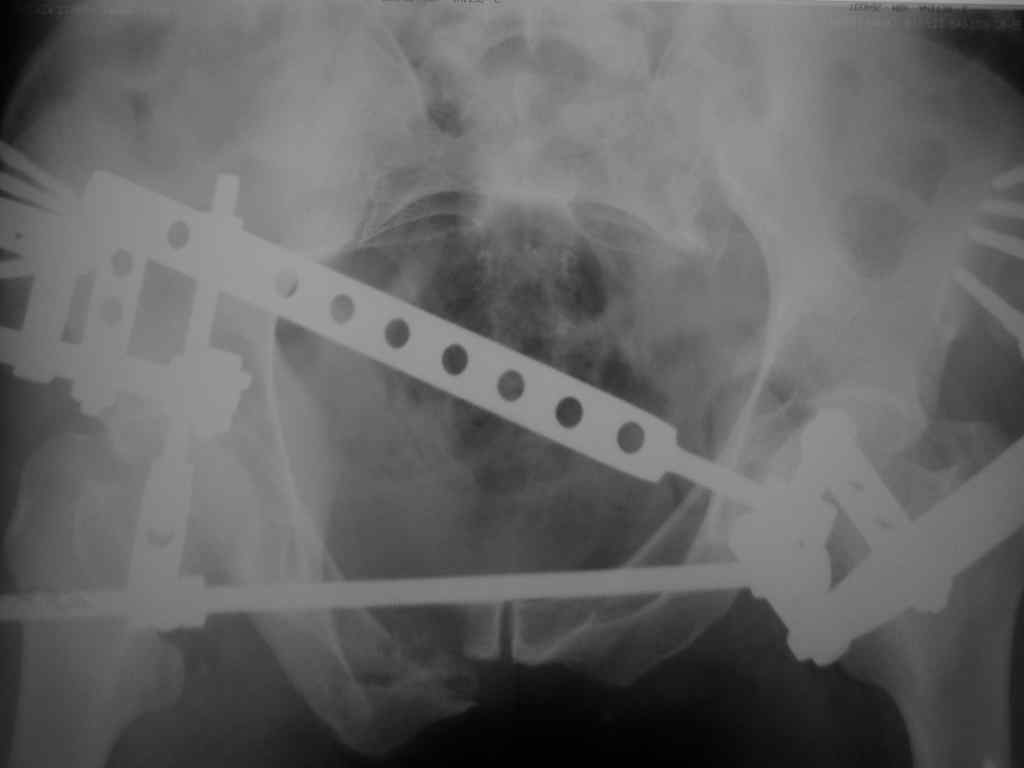

Можно посмотреть на нынешние снимки таза в аппарате, фас и inlet?

Отправитель: Владимир Бахарев 16 Ноябрь 2006, 12:13

Снимки вот

> (перелом лонной, седалищной костей справа . Разрыв КПС слева)

может быть и двустороннее повреждение задних отделов

> извинямси за качество R-грамм).

> Сохроняется смещение. Попытаемся его устранить этапно, но сомневаемся,

> хватит ли жесткости АВФ, и нет нигде методики введения илиосакральных

> винтов! Подскажите другие варианты!

по представленным рентгенограммам понять почти ничего невозможно из-за низкого качества, снимки идут в динамике? Для уточнения характера повреждения таза необходимо сделать хотя бы "inlet". повреждение представляется вертикально-нестабильным, в этом случае устранить краниальное и, возможно, передне-заднее смещение "передней рамой" невозможно и дело тут не в жесткости АВФ. Кольцевой опорой можно сделать все что угодно.